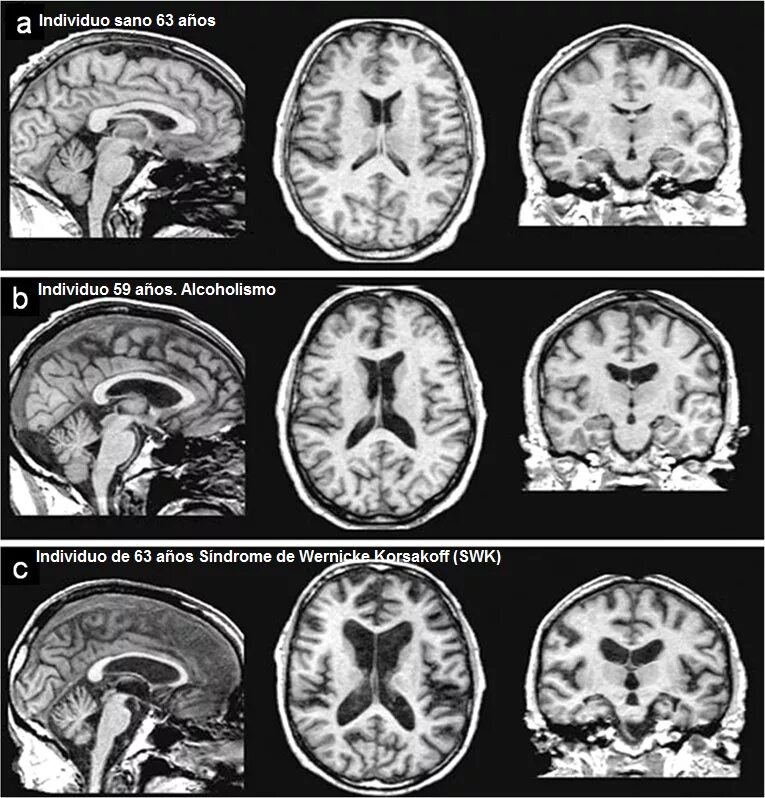

После мрт головного мозга